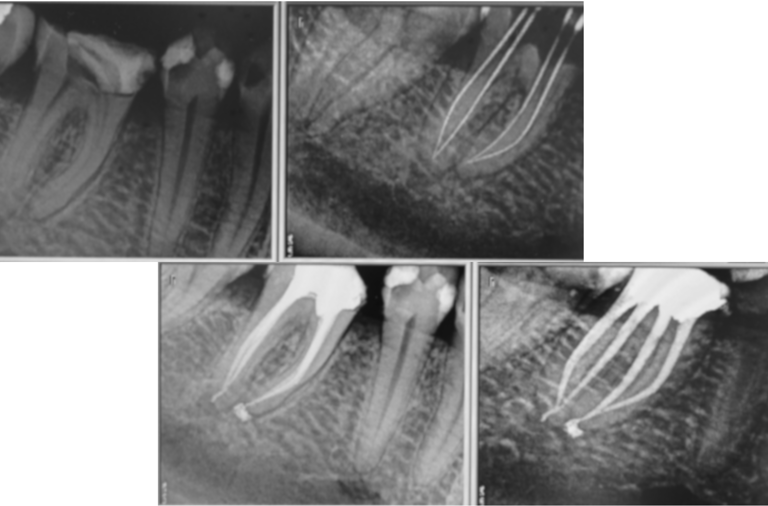

Le traitement endodontique constitue une étape clé de la pratique quotidienne de l’omnipraticien. Cette formation, proposée sous forme d’audit clinique, vous permet d’analyser vos pratiques de manière structurée et objective, en les confrontant aux recommandations actuelles et aux données scientifiques récentes.

L’objectif est d’identifier les écarts entre votre pratique quotidienne et les bonnes pratiques validées, afin d’améliorer la qualité de vos soins endodontiques et d’assurer des résultats prévisibles pour vos patients.

La réalisation du traitement : isolement, mise en forme, irrigation et obturation.

Le suivi : contrôler la réussite à long terme, tant cliniquement que radiographiquement.